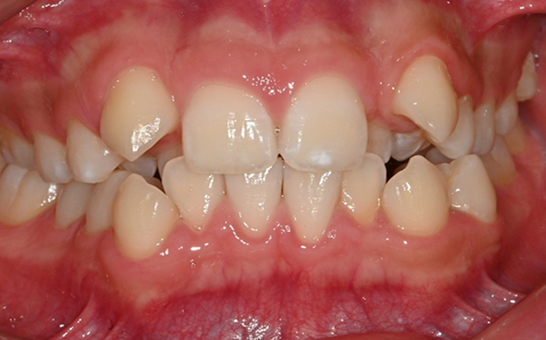

인비절라인 퍼스트(Invisalign First)는 어린이와

성장기 청소년을 위한 투명 교정 장치로, 치아와 턱뼈가

성장하는 과정에 맞춰 설계된 교정 시스템입니다.

해당하는 증상이 있다면 전문의와 상담 후 조기 교정 시

성장기 어린이에게 교합이 틀어지는것을 미리 예방 할 수 있습니다.

영구치가 나오는 과정에서

공간이 부족한 어린이

앞니의 심한 돌출이나

비대칭으로 인한 기능적

문제가 있는 어린이

턱 성장에 맞춰

치아 교정이 필요한 경우

기존 금속 교정 장치가

부담스러운 어린이와 부모님

※ 바른선택치과의원은 의료법을 준수하며 위 케이스는 실제 내원 환자분의 동의하에 공개된 사진과 동일한 환자분께 같은 조건에서 촬영한 사진을 활용했습니다.

개인에 따라 진료 및 치료 방법이 다르게 적용할 수 있으며, 효과와 부작용이 개인마다 다르게 나타날 수 있는 점을 안내해 드리며, 진료 전 전문의료진과 충분한 상담을 권해드립니다.